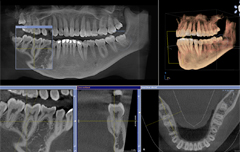

CTで診断することにより、従来のレントゲンではわかることができなかった、歯や顎の骨の詳しい状態を正確に把握する事ができます。埋伏している親知らずの状況を正確に把握する事で、安全な抜歯が可能です。また、インプラント治療においては、顎の骨の情報を正確に知ることで、安全で質の高い治療を提供する事ができます。

インプラントとCT

インプラントを埋入する部位の骨の状態(質や厚み、高さ、形態など)が十分な状態であるか、3D映像にて的確に判断することができ、患者さまにも十分ご理解いただくことが可能です。

歯科用CTでの撮影画像をもとに、的確な治療計画を立てることは、安心な治療への第一歩です。